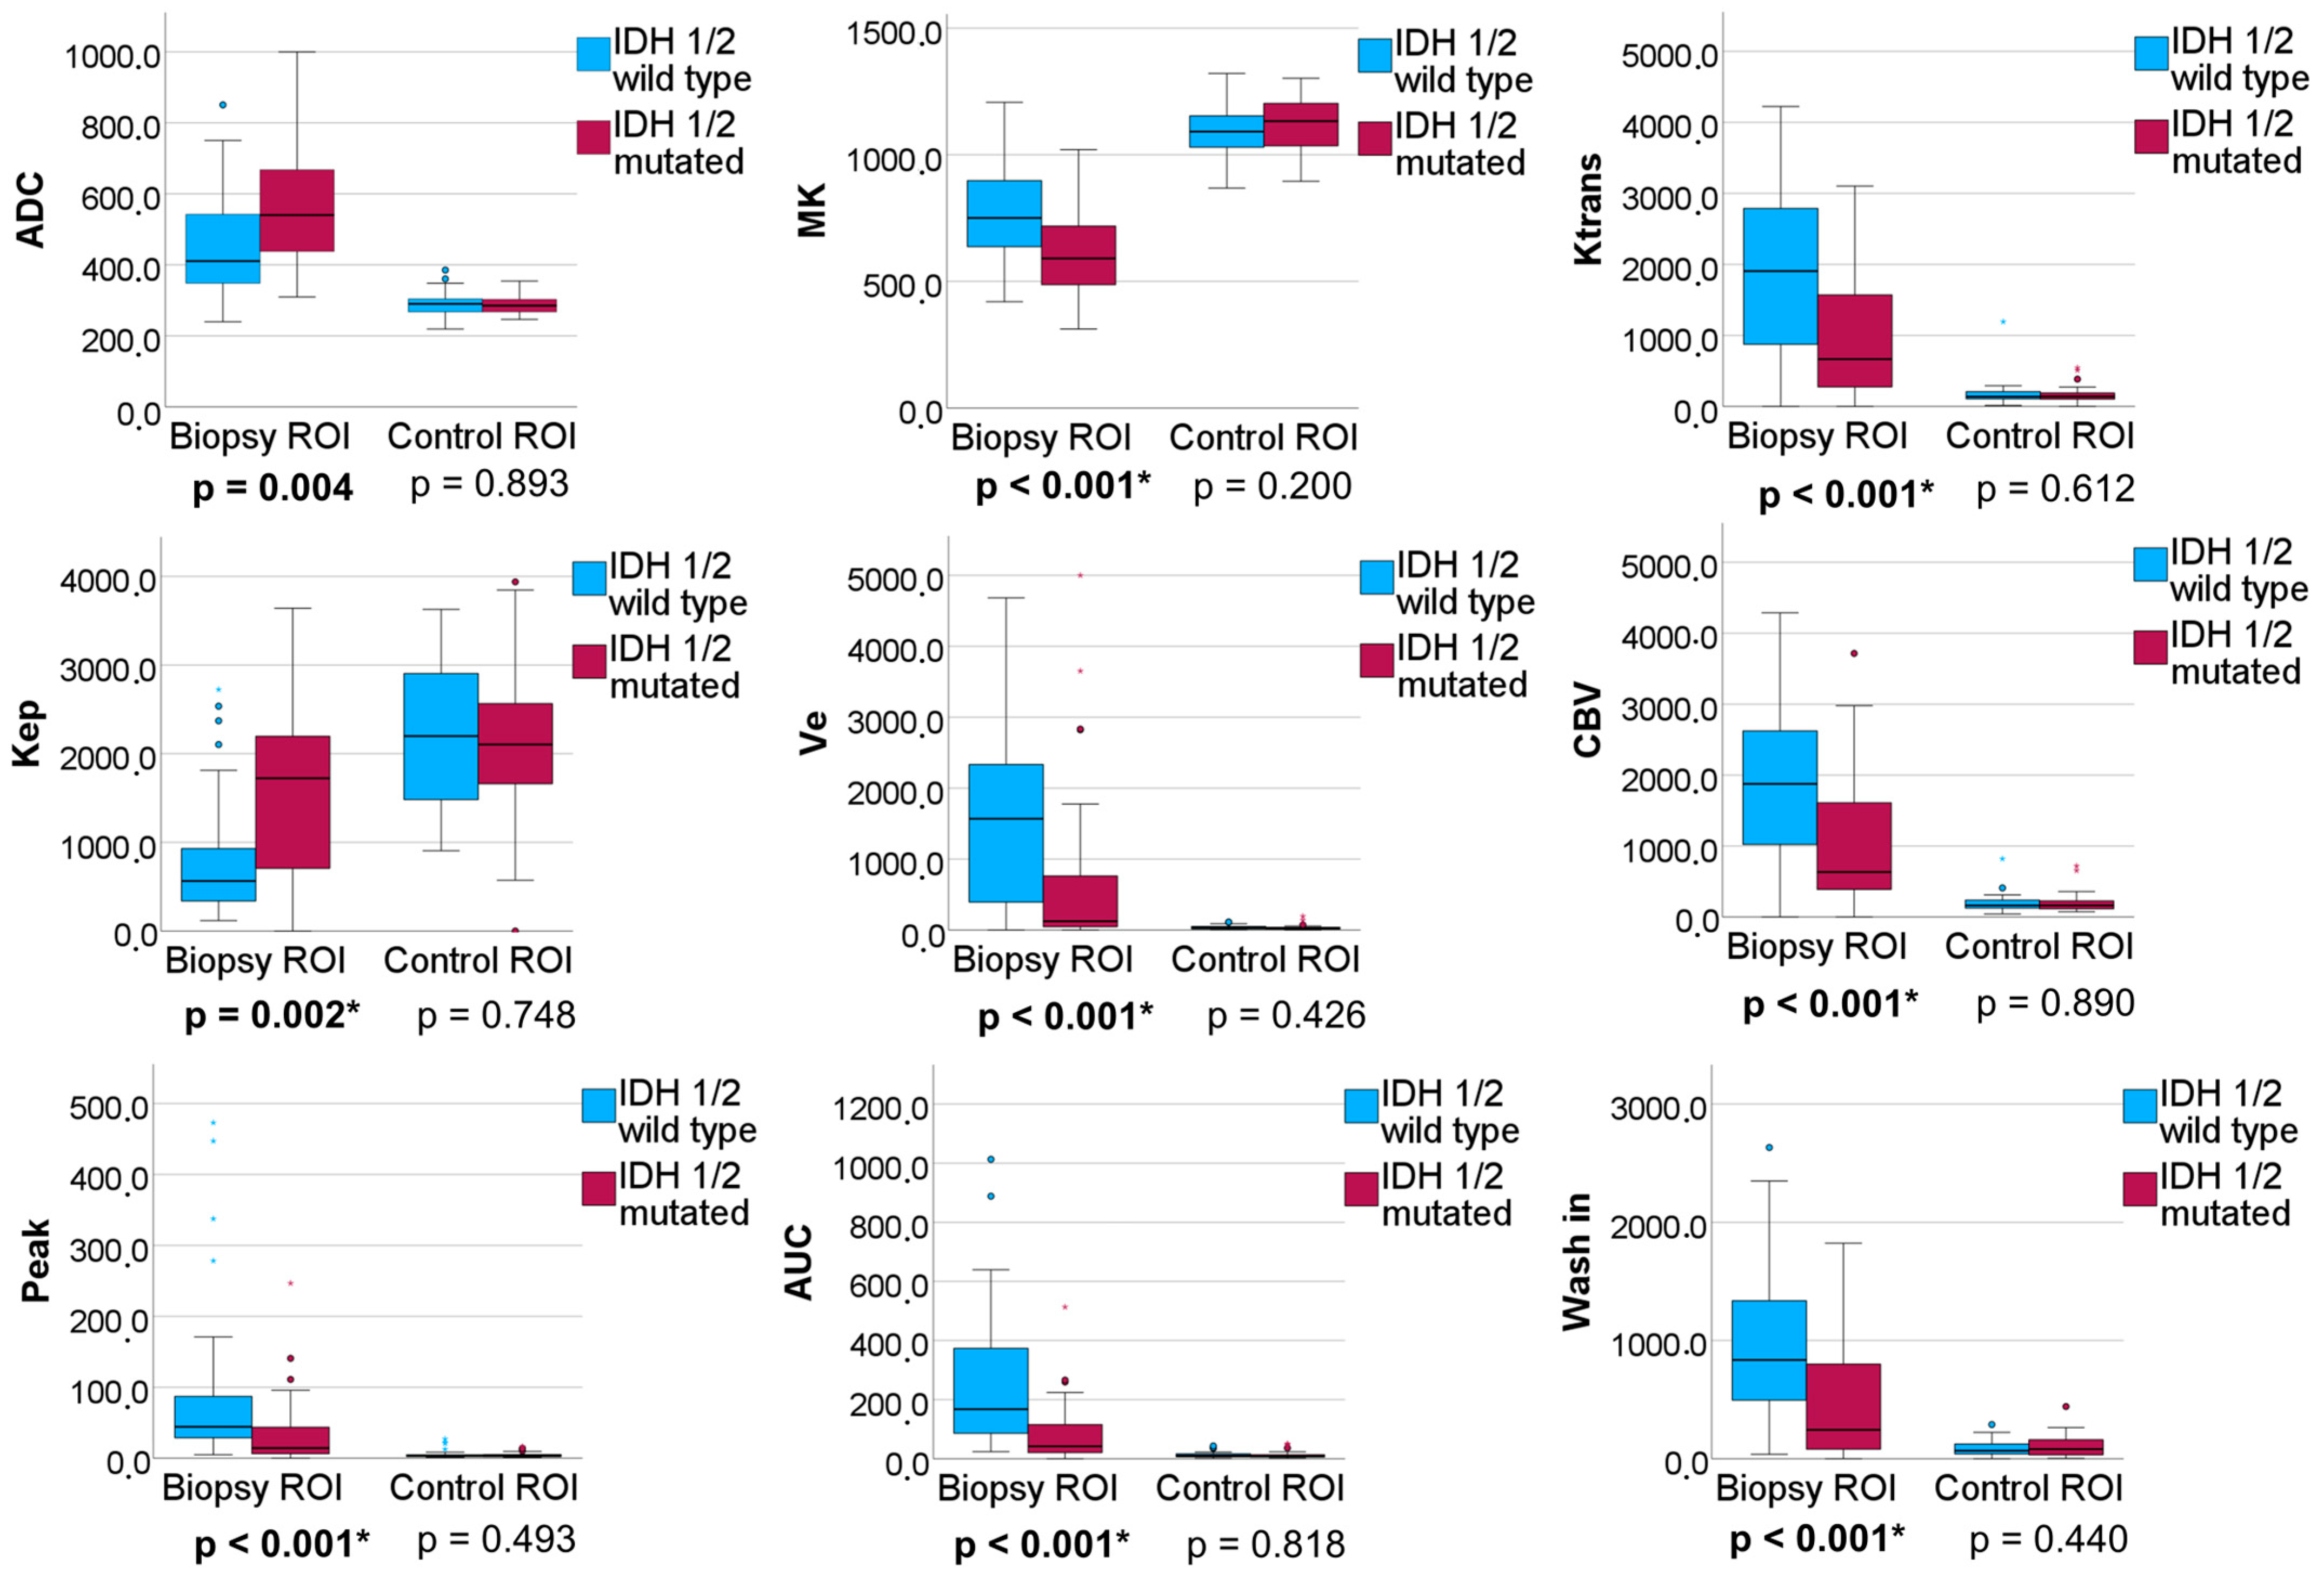

3.2.2. IDH 1/2 Mutated versus IDH 1/2 Wildtype Gliomas

| IDH1/2 Wildtype vs. IDH1/2 Mutated Adult-Type Gliomas | ||||||

|---|---|---|---|---|---|---|

| AUC (95% Confidence Interval) | p-Value | Cut-Off Value 1 | Sensitivity | Specificity | AIC | |

| Ktrans | 0.731 (0.614–0.849) | 0.001 | 1692.2 | 0.810 | 0.594 | 89.848 |

| Kep | 0.710 (0.588–0.831) | 0.002 | 842.3 | 0.667 | 0.750 | 91.636 |

| Vp | 0.583 (0.441–0.724) | 0.226 | 1303.0 | 0.833 | 0.500 | 99.564 |

| Ve | 0.726 (0.604–0.848) | 0.001 | 366.3 | 0.643 | 0,781 | 94.220 |

| CBV | 0.738 (0.622–0.854) | <0.001 | 1734.6 | 0.810 | 0.625 | 91.196 |

| TTP | 0.685 (0.562–0.807) | 0.007 | 2000.3 | 0.714 | 0.688 | 95.088 |

| Peak | 0.738 (0.625–0.850) | <0.001 | 13.0 | 0.500 | 0.938 | 94.056 |

| AUCDCE | 0.791 (0.609–0.891) | <0.001 | 118.8 | 0.762 | 0.688 | 83.677 |

| wash in | 0.718 (0.602–0.834) | 0.001 | 439.5 | 0.619 | 0.813 | 92.798 |

| wash out | 0.555 (0.419–0.692) | 0.416 | 1.0 | 0.786 | 0.406 | 103.058 |

| ADC | 0.699 (0.576–0.821) | 0.004 | 468.8 | 0.738 | 0.656 | 94.858 |

| MK | 0.718 (0.601–0.835) | 0.001 | 620.9 | 0.595 | 0.781 | 91.430 |

| AUCDCE and MK 2 | 0.802 (0.702–0.903) | <0.001 | 0.6 | 0.762 | 0.759 | 80.982 |